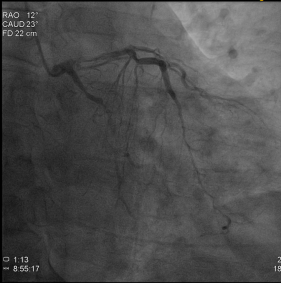

唐先生因为急性胸痛到桂林市某三甲医院诊断急性心梗,冠脉造影检查提示RCAp(右冠状动脉近段)慢性闭塞,LMd(左主干远端)95%狭窄,血管病变极为严重,支架手术风险极大,该院建议冠脉手术搭桥。

辗转多个医院仍得不到满意的解决方案,唐先生慕名找到桂林医学院第二附属医院心血管内科二病区副院长夏中华和科室主任王新云带领的团队,因考虑到患者年仅42岁,而搭桥手术的桥血管使用年限不长,手术团队对患者进行了全面的心脏支架植入术前评估。

为了满足患者及家属的愿望,提高年轻患者的生活质量,延长患者的生命,王新云团队为患者进行了周详的术前准备,因为唐先生右冠闭塞,左侧无保护病变,在充分评估手术风险以及与患者家属充分沟通后,决定分两期为他实施手术。第一次手术----右冠CTO病变的处理,手术过程十份艰难,面对这样复杂的病变,王新云熟练地操作着微导管、穿通导管、导引延伸导管及多种CTO导丝。手术非常顺利,成功地开通了右冠脉的CTO病变,并在血管内超声(IVUS)的指导下顺利植入了支架。有了这支血管的保驾护航,再次为患者实施了第二次手术:左主干+前三叉血管病变处理,两期手术都获得巨大成功,让唐先生重获了新生。